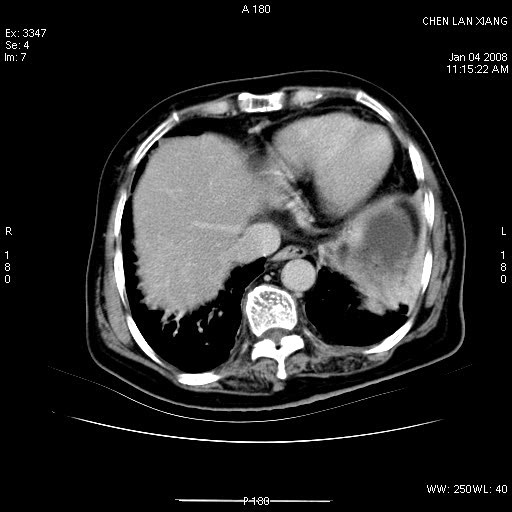

标题: CT11180:女,76岁,腹痛3-4天 [打印本页]

女,76岁,腹痛3-4天,b超示:肝内实性肿物,胆囊强回声,胆总管扩张.

考虑:1、胆总管下端结石伴梗阻性肝内外胆管扩张(肝左叶外侧段肝内胆管多发结石、胆管炎);

2、肿囊癌累及肝,不除外 黄色肉芽肿性胆囊炎。

1 胆总管末端结石伴肝内胆管结石,肝内外胆管扩张。2 胆囊扩大,胆囊壁不规则增厚,内见软组织密度影。考虑:慢性胆囊炎,不除外胆囊癌!

胆总管末端结石伴肝内胆管结石,肝内外胆管扩张。低位胆道梗阻2 胆囊扩大,胆囊壁不规则增厚,内见软组织密度影。考虑:慢性胆囊炎,不除外胆囊癌!

胆囊内结增强影,肝内胆管、胆总管扩张明显。肝内胆管、胆总管下段多发结石,胆囊癌,建议mrcp检查

肝内外胆管多发结石;胆囊癌;

胆囊密度增高,增强后周边肝组织及胆囊窝下部周边软组织延时性不规则强化.然胆囊壁未见明显不规则增厚及肿块.左侧肝内胆管及胆总管下段结石伴胆系扩张.

考虑;胆囊炎(黄色肉芽肿性胆囊炎?),左侧肝内胆管及胆总管下段结石.

ct所见:1、 肝内胆管结石,肝内外胆管扩张。低位胆道梗阻,胆总管下端结石;2 胆囊扩大,胆囊壁不规则增厚

考虑:胆总管下端结石并肝内外胆管扩张,肝内胆管结石;

慢性胆囊炎

标题: 肝右叶病灶

胆囊癌侵犯肝右叶?

1)胆囊癌伴肝脏转移。2)胆总管下端结石、肝内胆管结石伴肝内外胆管扩张。